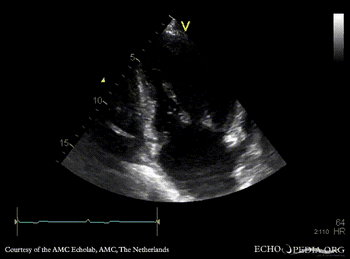

| PLAX: dilated aortic root, redundant mitral valve leaflets

PLAX: dilated aortic root